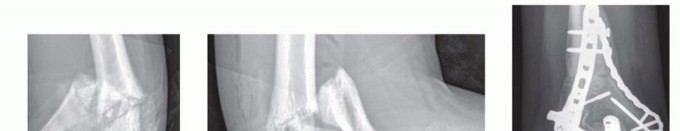

FIG 2 • A,B. A 15-year-old boy with type IIIA open distal humerus comminuted T-condylar humerus fracture. C,D. Three months following open reduction and internal fixation with olecranon osteotomy. Range of motion 0 to 140 degrees with no pain. Older children and young adolescents will often require an open approach. Comminution in the fossa may necessitate an olecranon osteotomy (FIG 2).Generally, pediatric fractures are less comminuted than adult fractures and may not require a full osteotomy.A Morrey slide approach is used in such a case where the triceps and ulnar periosteum are elevated off the ulna medially to expose the distal humerus without performing an osteotomy.3It was originally described to avoid olecranon osteotomies in cases where total elbow replacement would be a salvage operation.It can be useful in adolescents because the fractures are not as comminuted, but excellent visualization of the joint is desirable to provide anatomic reduction and restoration of elbow function. FIG 3 • A. A 13-year-old boy with a T-condylar humerus fracture with coronal split of the capitellum. B.